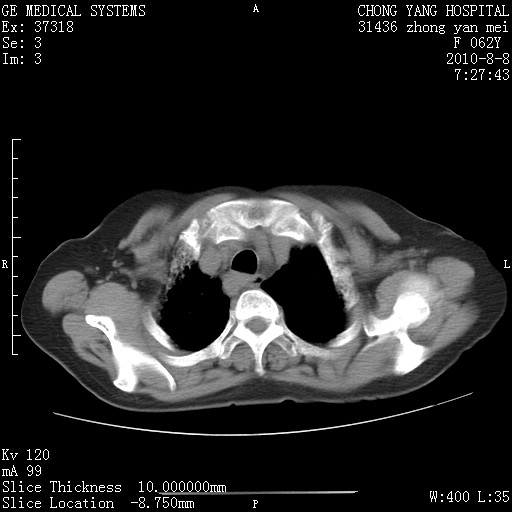

标题: CT28269:F62Y咳嗽胸痛数月。 [打印本页]

标题: CT28269:F62Y咳嗽胸痛数月。

3.迷走右锁骨下动脉。

1.肺间质纤维化.

2.纵隔淋巴结肿大。